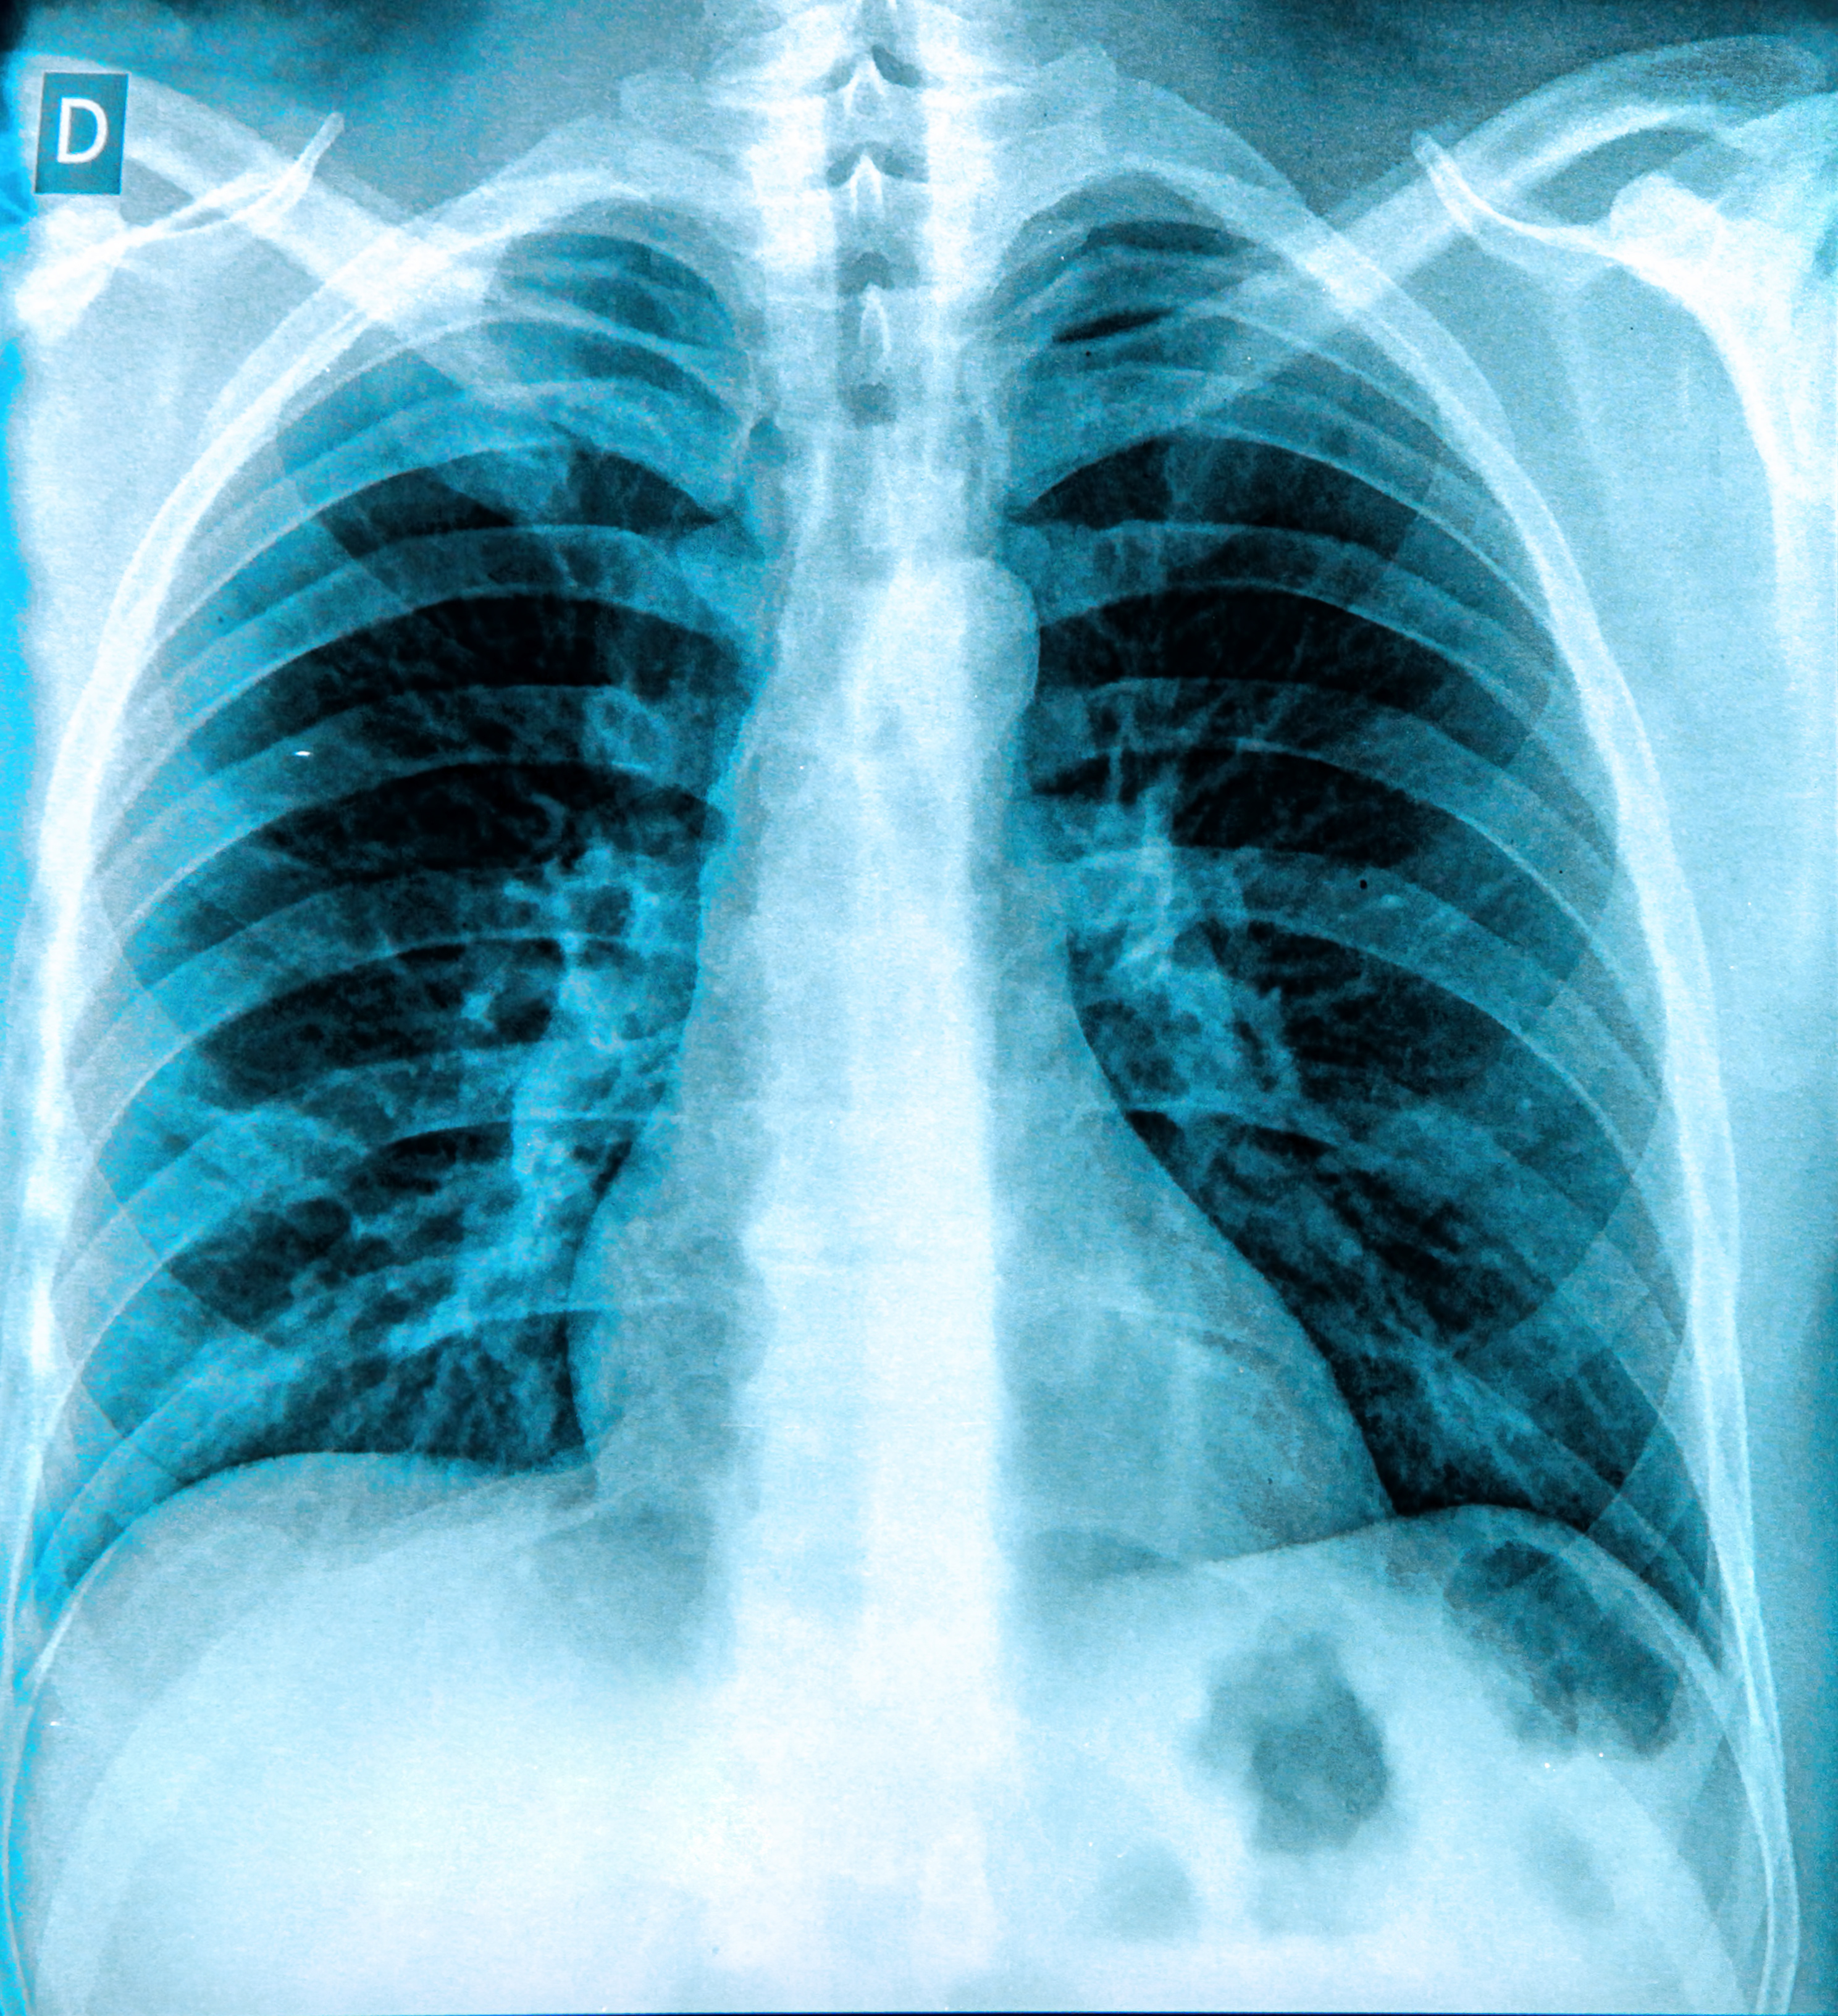

KA Imaging plans to invest $1.5 million to develop a dual-energy mobile x-ray system, based on the company's Reveal 35C detector.

The dual-energy system will give patients in critical care and those located in rural or remote areas better access to imaging, the company said.